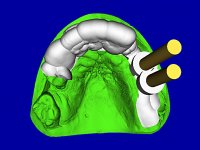

O estudo imagiológico para a colocação dos implantes, começou com a realização em laboratório de uma guia com dentes em sulfato de bário. Esta guia foi colocada em boca conjuntamente com marcas de referência coladas aos dentes, também em sulfato de bário. A guia foi estabilizada com cera mole. A TAC foi realizada com estas referências colocadas em boca. Após a realização da TAC foi feita uma impressão de arrasto em silicone. Esta impressão foi vazada a gesso em laboratório e posteriormente digitalizada. A digitalização do modelo com as referências foi sobreposta á imagem da TAC, permitindo uma planificação apurada na colocação dos implantes. Na planificação foi decidido colocar 2 implantes no local dos dentes 2.3 e 2.4 evitando-se a zona do 2.2 com pouco osso e o seio maxilar. Este estudo deu origem a uma guia cirúrgica que orientou a colocação dos implantes. Durante o período de osteo-integração a paciente utilizou a prótese removível rebasada com acondicionador de tecidos. A guia cirúrgica mostrou-se também útil na exposição dos implantes mostrando a sua localização precisa e orientando a incisão. A impressão definitiva foi realizada utilizando a técnica de moldeira aberta após eliminação do attachment. No laboratório foi confeccionada uma ponte metalo-cerâmica de 3 elementos com o elemento 2.2 em suspensão. A ponte após verificação e aprovação foi cimentada. A reabilitação apesar de pouco extensa (sem o elemento 2.6) mostrou-se capaz estetica e funcionalmente.